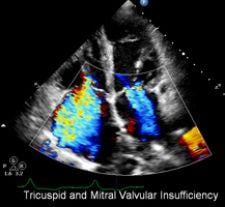

Primarily designed for echocardiography, the CX50 was made with many of the same features from Philips’ iE33 echocardiography system, providing clinicians a portable ultrasound that can be used for diagnosis, according to Philips.

The company said the system features the PureWave transducer, which produces greater bandwidth and efficiency, yielding better imaging performance. This technology is designed to achieve greater penetration in patients who are traditionally difficult to image, such as obese patients or patients with emphysema. The system also features XRES adaptive imaging that reportedly reduces noise and artifact, producing greater clarity, according to the company.